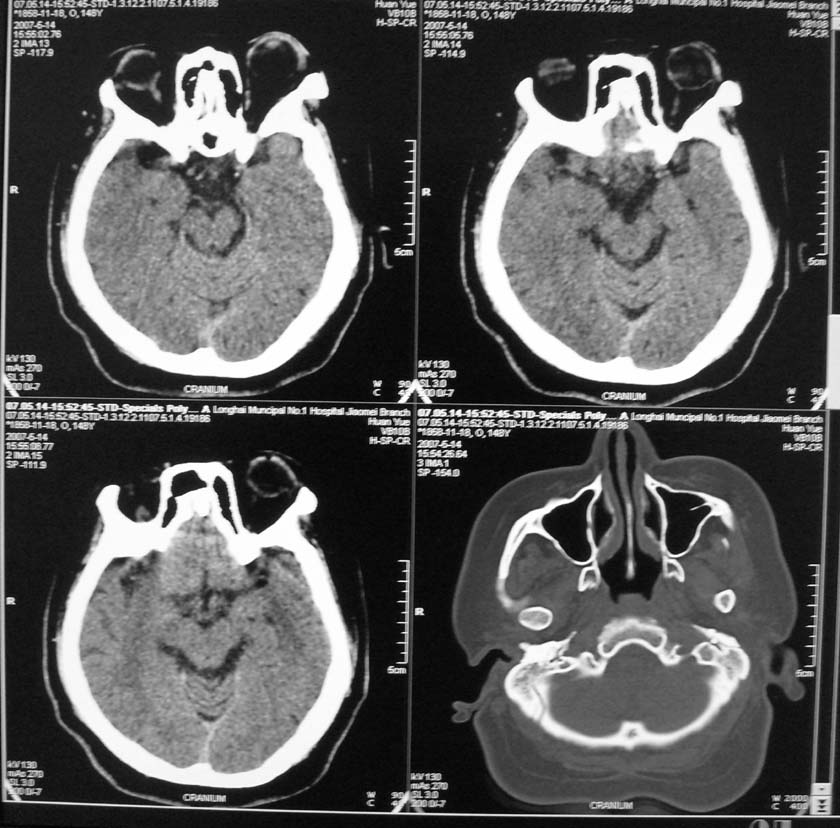

以下是引用天南地北在2007-5-15 23:30:00的发言:[br]看不出来什么[br]建议冠面增强扫描,或mri检查

以下是引用郭凯在2007-5-16 0:17:00的发言:[br]看不到,如果临床支持的话还是做mri看一下吧,对垂体微腺瘤比较敏感.[br]ct上看不到不能乱报.

以下是引用jiangjing在2007-5-16 11:06:00的发言:[br]看不出来什么[br]建议冠面增强扫描,或mri检查